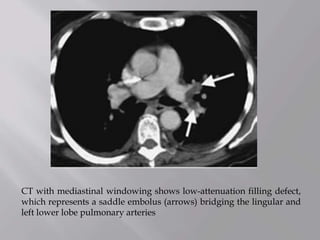

CT with mediastinal windowing shows low-attenuation filling defect,

which represents a saddle embolus (arrows) bridging the lingular and

left lower lobe pulmonary arteries